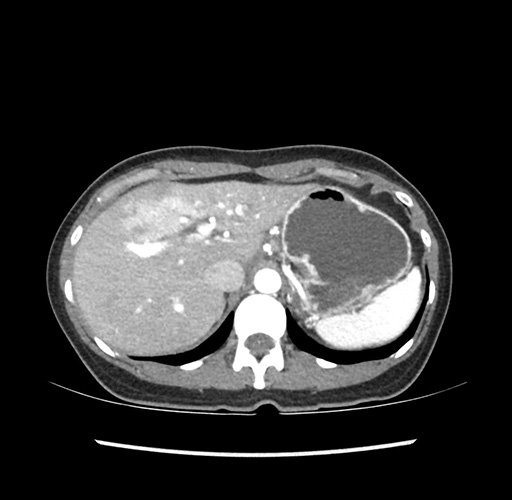

Imaging Analysis

Look through the patient's CT scan to identify any areas of concern for the necessary procedure.

Based on your CT findings, which issue(s) would give reason for "planned slowing down moment(s)" in this case?

Considering a standard left lateral sectionectomy procedure, what step(s) of the operation would you do differently in this case ?